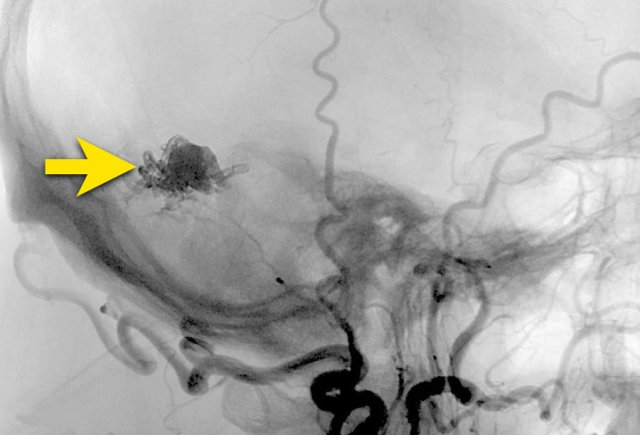

AVM 3

A 55 year old male presented with acute headache and a confused consciousness state.

NCCT shows a lobar parenchymal hemorrhage surrounded by edema (left image).

CTA only showed some dots of contrast (arrow) in the hemorrhage, connected to small abnormal vessels (not shown) below the hemorrhage.

No feeding arteries of draining veins were visible.

The mass effect of the hemorrhage can obscure the underlying cause in the acute phase.

DSA and 3D images from the Right Internal Carotid artery showed an underlying AVM.

• Feeding artery - black arrowheads

• Nidus of the AVM - yellow arrow

• Draining veins - blue arrows

Spetzler Martin 1

• small AVM < 3cm

• a non-eloquent area

• superficial venous drainage

DSA control after surgical removal of the AVM shows no signs of residue.